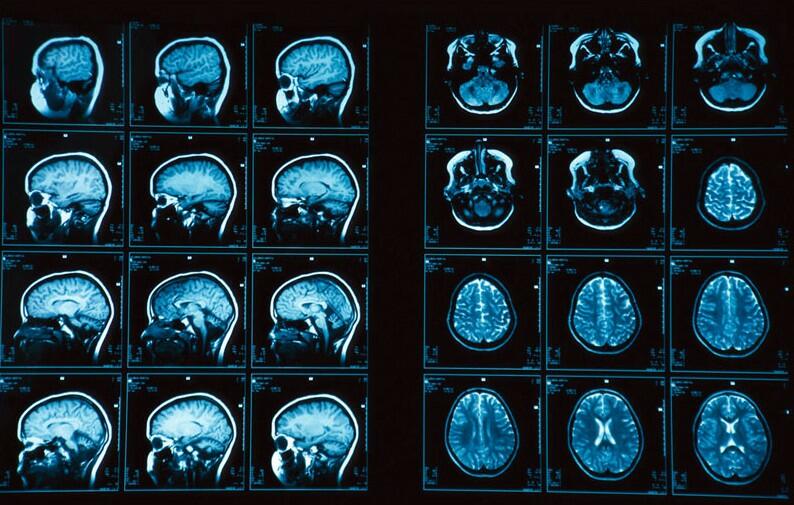

МРТ позволило увидеть признаки мигрени в мозгу человека

Ученые смогли увидеть вызванные мигренью изменения в мозгу с помощью МРТ. Об этом сообщает пресс-служба Радиологического общества Северной Америки, передает Day.Az со ссылкой на Gazeta.ru.

"У людей с хронической и эпизодической мигренью без ауры наблюдаются значительные изменения в периваскулярных пространствах мозга, в полуовальном центре", - заявляют медики. Это удалось выяснить с помощью МРТ с полем 7 тесла, в исследовании приняли участие 10 человек с хронической мигренью, 10 человек с эпизодической мигренью без ауры и пять здоровых людей того же возраста.

Периваскулярные пространства представляют собой заполненные жидкостью среды, окружающие кровеносные сосуды головного мозга. Статистический анализ показал, что у страдающих от мигрени людей расширенные периваскулярные пространств встречались гораздо чаще, чем у здоровых.

Ученые предполагают, что обнаруженные изменения связаны с проблемами лимфатической системы головного мозга. Однако неясно, является ли это следствием или причиной мигрени. Авторы работы надеются, что их исследование в итоге поможет лечить это заболевание.